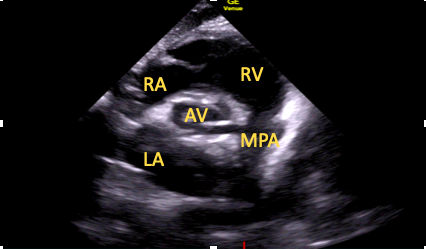

This should be the first short-axis view obtained using the above technique (Figure 7).15

Figure 7. Subcostal short-axis aortic view.

RA=right atrium, RV=right ventricle, AV=aortic valve LA=left atrium, MPA=main pulmonary artery